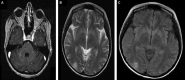

Posterior reversible encephalopathy syndrome (PRES) is a clinical-radiographic syndrome with seizures, headache, altered mental status and visual disturbances. It is typically associated with posterior cerebral white matter oedema on neuroimaging. There is an increasing number of cases of PRES reported with different chemotherapeutic protocols. However, PRES is rarely reported in association with irinotecan, fluorouracil and folinic acid (FOLFIRI). We report a 28-year-old female patient with a history of Stage IV gastric cancer who presented with abdominal pain and recurrent vomiting that was thought to be related to a partial intestinal obstruction secondary to peritoneal metastasis. Eventually, she was treated with FOLFIRI. A few hours after initiation of the fluorouracil infusion in the second cycle, she developed a tonic-clonic seizure. MRI of the brain showed multiple bilateral T 2 and flair hyperintense cortical and subcortical lesions suggestive of PRES. Other causes of PRES were excluded, as well as brain metastasis. Unfortunately, the patient developed septic shock and died a few days after her presentation.